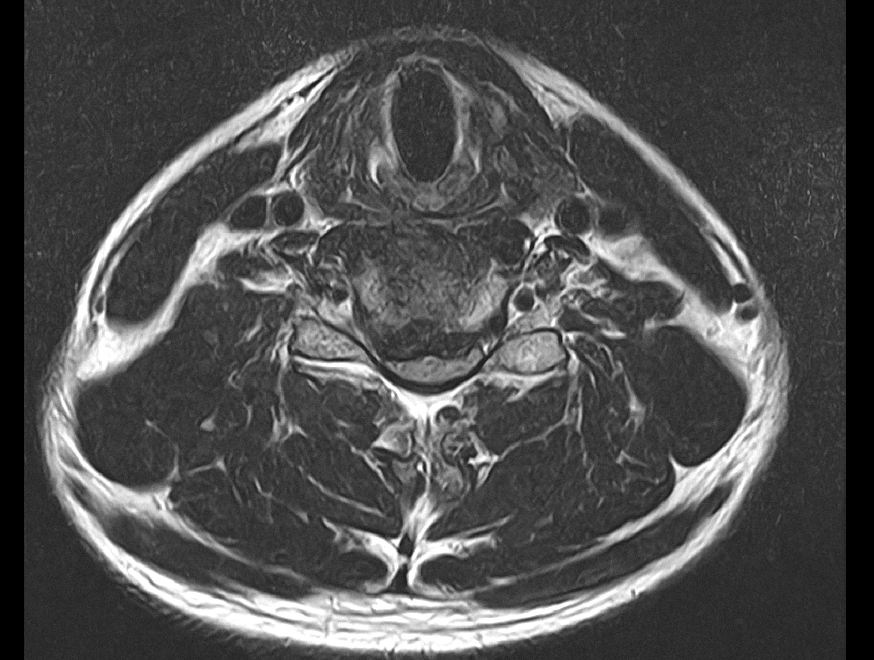

• 2번 째 사진

아마 올려주신 사진중에서 두번째 사진이 디스크가 가장 많이 튀어나온 부위의 단면일 거라고 예상됩니다.